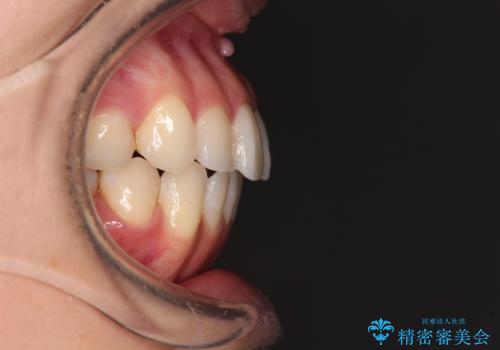

- 前歯のデコボコを気にして来院された患者様です。

主に下顎歯列全体の後方移動とIPR(歯と歯の間を削る)によってデコボコが解消するように設計し、インビザラインにより治療を行うこととしました。

舌突出癖がある方ですと、叢生が解消すると同時に前方に拡大されてしまいますが、ゴムかけをしっかりと行ってくださったこともあり、スッキリとした仕上がりとなりました。